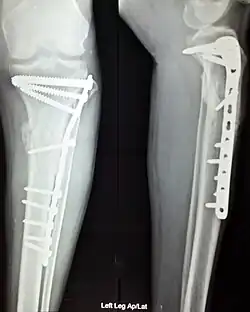

Internal fixation is an operation in orthopedics that involves the surgical implementation of implants for the purpose of repairing a bone, a concept that dates to the mid-nineteenth century and was made applicable for routine treatment in the mid-twentieth century.[1] An internal fixator may be made of stainless steel, titanium alloy,[2] or cobalt-chrome alloy.[3]

Open reduction internal fixation (ORIF) involves the implementation of implants to guide the healing process of a bone, as well as the open reduction, or setting, of the bone. Open reduction refers to open surgery to set bones, as is necessary for some fractures. Internal fixation refers to fixation of screws and/or plates, intramedullary rods and other devices to enable or facilitate healing. Rigid fixation prevents micro-motion across lines of fracture to enable healing and prevent infection, which happens when implants such as plates (e.g. dynamic compression plate) are used. ORIF techniques often are used in cases involving serious fractures such as comminuted or displaced fractures or, in cases where the bone otherwise would not heal correctly with casting or splinting alone.

Various techniques of minimally invasive surgery for internal fixation of bones have been reported. The treatment of fractures of the distal third of the tibia has evolved with the development of improved imaging and surgical techniques.[5]